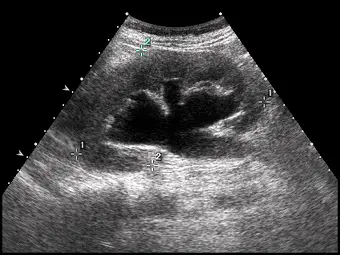

腎臟超音波掃描時,發現腎盂(renal pelvis)及多個腎盞(calyces)擴張如下圖,最有可能的診斷為何?

- 影像特徵:此為一張腎臟超音波(Renal ultrasound)的長軸切面影像。影像中可見腎臟中央的腎竇區域出現大範圍的「無回音區(anechoic area,即影像中的黑色區域)」,代表有液體聚積。

- 解剖對應:這些無回音區並非獨立存在,而是呈現互相連通的分支狀(branching pattern)。中央較大的無回音區為擴張的腎盂(dilated renal pelvis),向外延伸的囊狀構造為擴張的腎盞(dilated calyces)。

- 典型徵象:這種擴張的腎盂與多個腎盞相通的影像,在超音波下常被形容為「熊爪徵(Bear claw sign)」或花椰菜狀,為典型的中度至重度「腎水腫(Hydronephrosis)」表現。周邊仍可見到被擠壓的腎臟實質(renal parenchyma)。